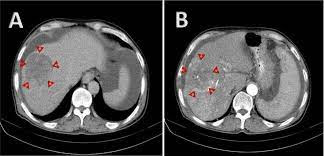

HCC (Primary cancer of the liver)

Hepatocellular carcinoma HCC primarily arises in a cirrhotic liver where chronic injury leads to repeated inflammation fibrin oh genesis and disordered liver architecture cirrhotic livers exhibit focal lesions areas of abnormal immature hepatocytes that are predisposed to malignant transformation chronic viral infections such as hepatitis b and c also promote carcinogenesis through enhanced hepatocytes turnover and increased mutation rates hepatocellular carcinomas are phenotypic ly and genetically heterogeneous tumors driven by diverse molecular mechanisms the identification of common genomic alterations has led to the development of targeted therapies that suppress hepatic carcinogenesis through multiple pathways multi kinase inhibitors have been developed that simultaneously target key regulators in angiogenesis, tumorigenesis and metastasis hepatocellular carcinoma is a hyper vascular tumor the initiation growth and metastasis of HCC relies on angiogenesis the formation of new blood vessels from pre-existing vascular beds genetic changes in local hypoxia in tumors leads to the secretion of soluble angiogenic factors that activate resting and öthey lleol cells in adjacent blood vessels these angiogenic factors such as vascular endothelial growth factor are up-regulated in most human tumors to help supply adequate oxygen and nutrients to the growing tumor Veg F binds to the Veg F receptor a tyrosine kinase receptor located on endothelial cells that promotes the activation proliferation and migration of these cells tumor induced up regulation of Veg F is associated with increased tumor growth and poor prognosis several multi kinase inhibitors have been developed that block the activity of veggie afar reventing the formation of new blood vessels and tumors fibroblast growth factor is also up regulated in the majority of HCC cases FGF and Veg F act synergistically to stimulate tumor induced neovascularization FGF has also been implicated in tumor cell proliferation survival and invasion inhibition of this signaling pathway induces apoptosis of HCC cells lenva-Deneb and reco raffinate blocked the activity of the FGF receptor decreasing tumor vascularization and proliferation another angiogenic factor platelet derived growth factor is required for the recruitment of smooth muscle cells and parasites that surround and support new blood vessels several multi kinase inhibitors including lenva Deneb serotonin and reco raffinate limit neovascularization by blocking the activity of the PDGF receptor multi kinase inhibitors may also prevent tumor growth and proliferation by blocking the activity of several other tyrosine kinase receptors such as kit or ret activation of tyrosine kinase receptors initiates complex intracellular signaling pathways that promote cell growth proliferation survival and differentiation these receptors are often over expressed or mutated in cancer cells tumor progression usually involves the action of multiple kinase pathways and targeting several receptors simultaneously with multi kinase inhibitors may provide a synergistic effect and reduce the possibility of drug resistance.